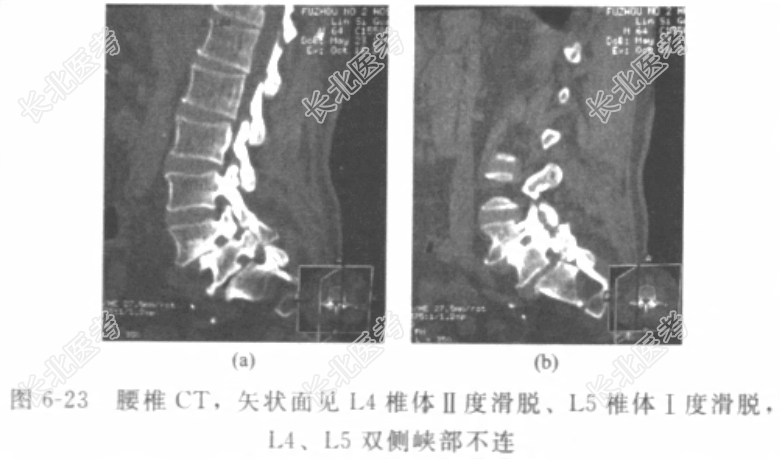

[材料题] 患者男性,50岁,因“反复腰痛二十余年,加重伴右下肢跛行3个月”入院。腰部疼痛二十余年,劳累时加重,休息后缓解。3个月前劳作后腰痛加重,伴有右下肢麻木、疼痛。步行约200m需下蹲休息才能缓解麻木、疼痛。经非手术治疗症状无明显缓解。患者既往体健,否认其他“心、肝、肺、脾、肾”等重要脏器疾病史,否认传染性疾病史,否认外伤史、输血史,否认食物、药物过敏史。体格检查:T37.0℃,P78次/分,R20次/分,BP130/70mmHg。神志清楚,腰椎生理前凸增大,腰3/4棘突间扪及台阶样改变。右大腿后外侧、右小腿前外侧、右足背内侧皮肤感觉减弱,右伸拇趾肌力较对侧稍减弱。右直腿抬高试验,可抬高60°,为阳性,加强试验阳性。辅助检查:腰椎X线片(图6-22)示腰4、腰5椎体前滑脱,腰4及腰5可疑峡部裂。 入院诊断:腰4、腰5滑脱症,腰4、腰5双侧峡部裂。诊疗计划:完善检查,积极术前准备。患者常年从事拉板车、抬石头等重体力劳动,有下腰痛病史二十余年,休息或口服镇痛药缓解。3个月前劳作后腰痛加重,伴有右下肢麻木、疼痛。步行200m需下蹲休息才能缓解。经过休息及外院按摩、理疗等,仍有腰痛伴右下肢麻木、疼痛。无法长距离行走,约200m就需要下蹲休息。患者行腰椎CT三维及MRI检查,如图6-23、图6-24。